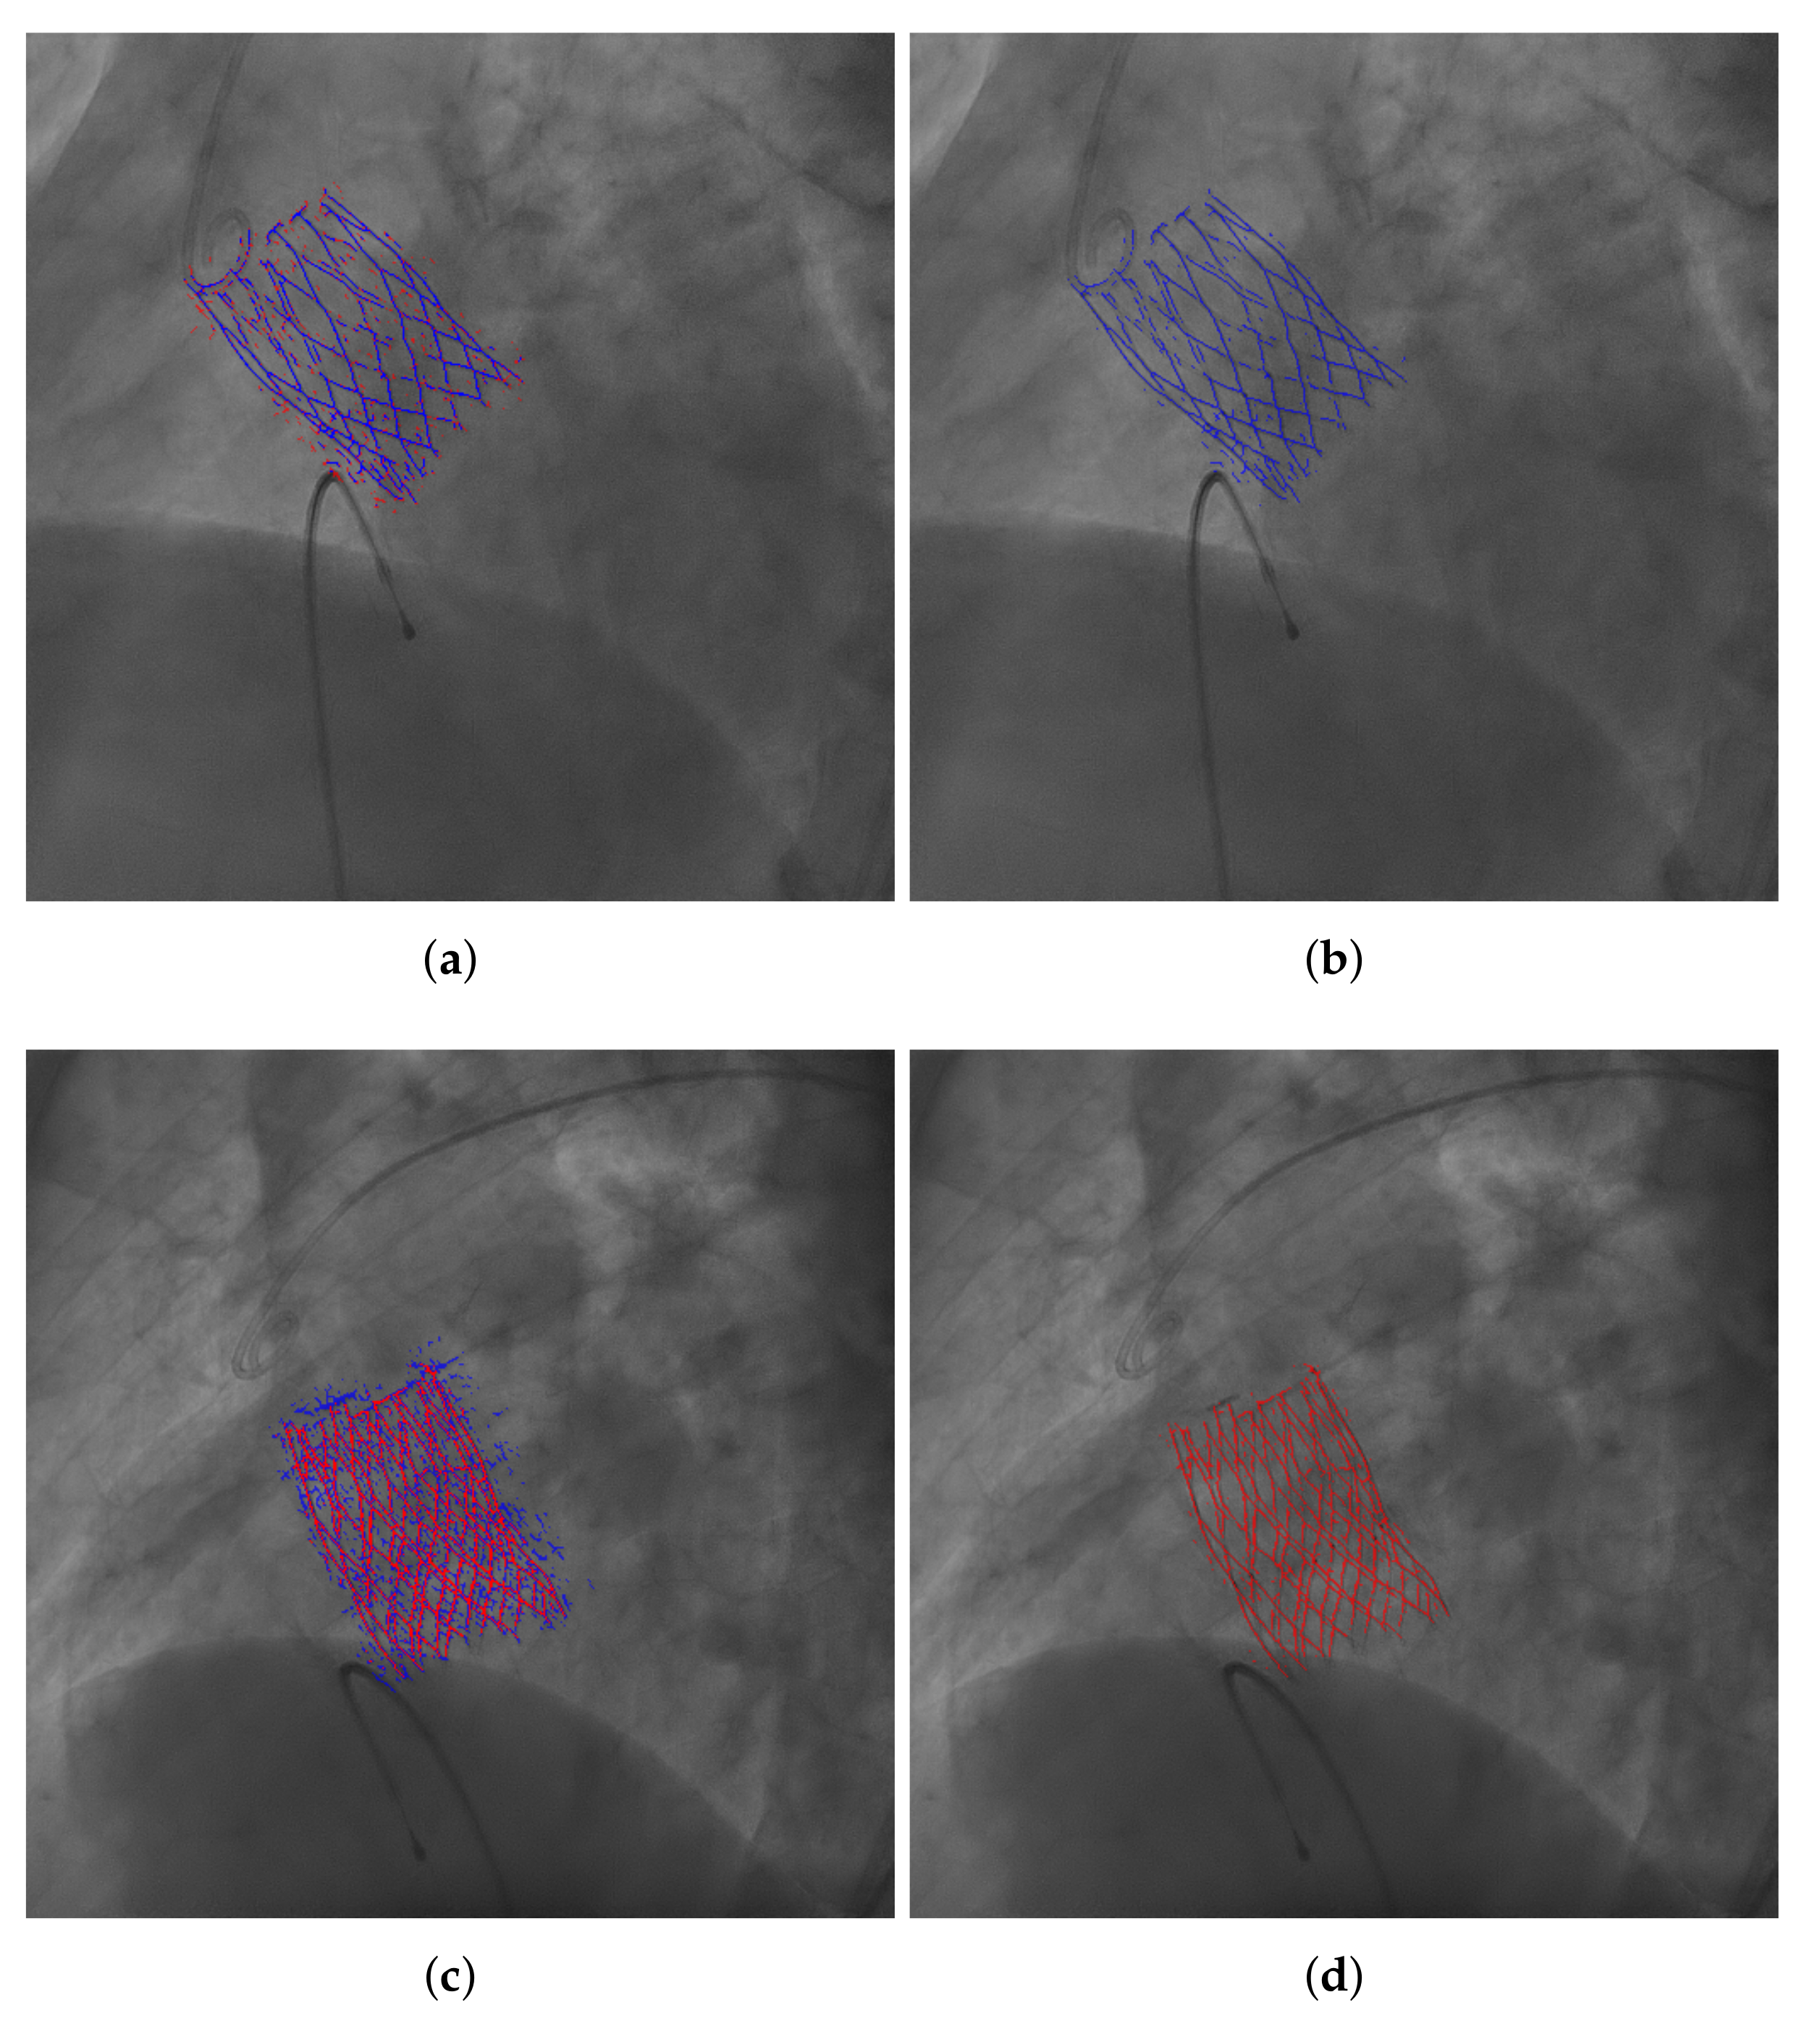

3.4. Evaluation of the Segmentation Results